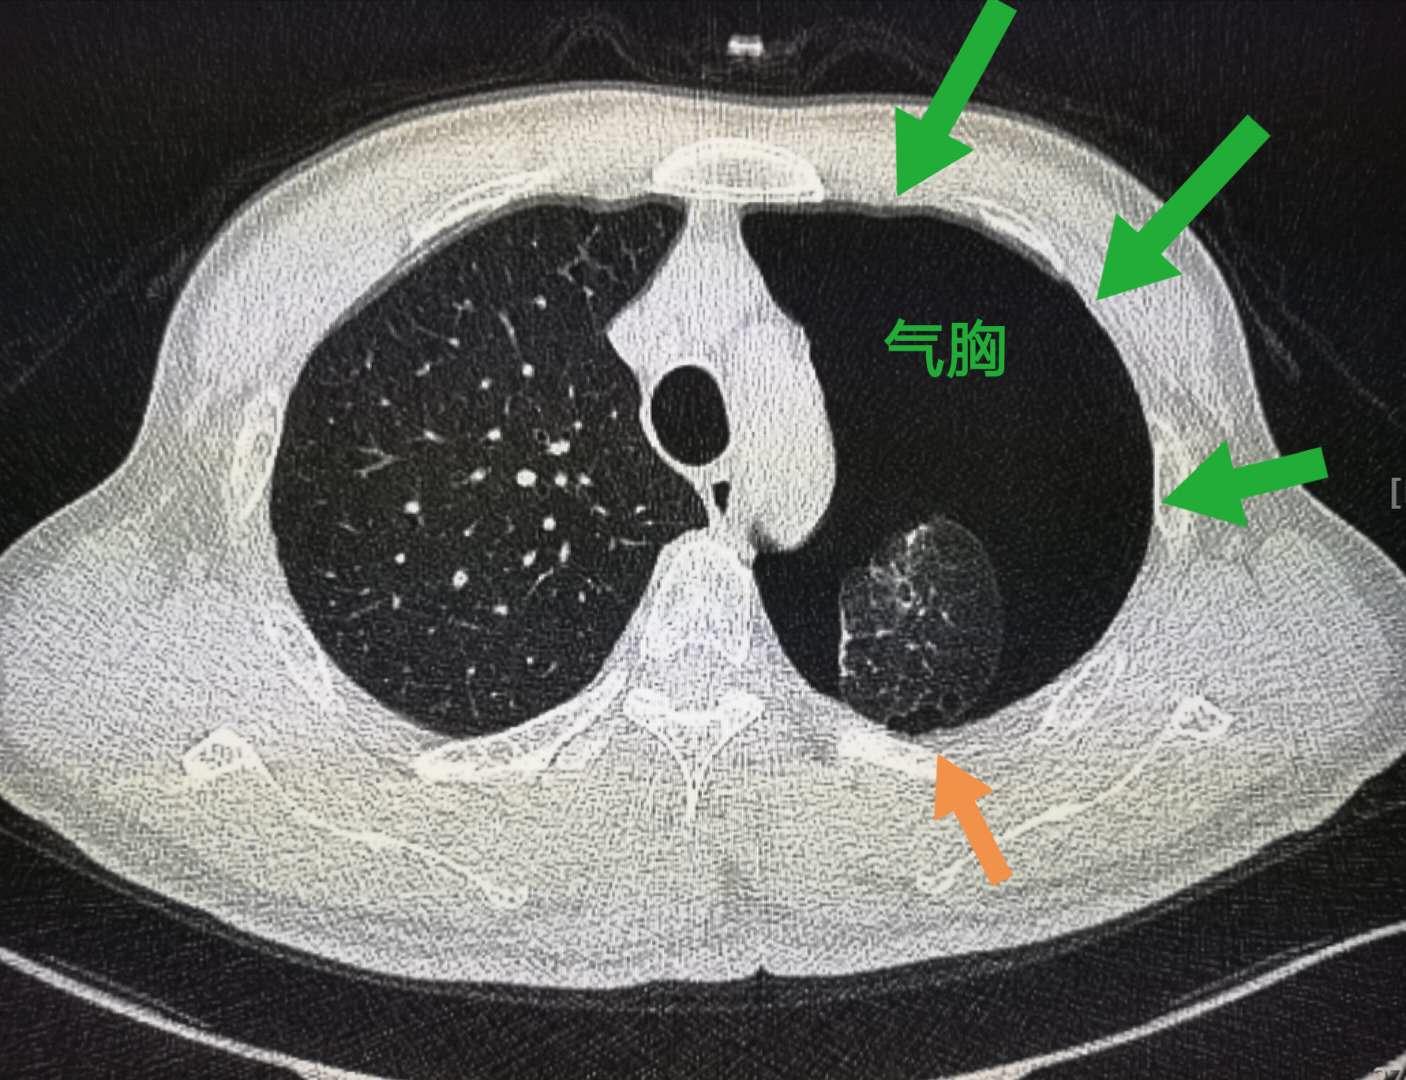

像上图这个小伙子就相对幸运一点,肺尖部胸膜下的肺大泡(橙色箭头)破裂,引起自发性气胸,没有伴发出血,经导管引流后顺利出院了。

原发性自发性气胸是指无明确肺部疾病,在无诱发事件的情况下发生的气胸。常见原因就是上面这个病例,是由胸膜下肺大泡破裂所致。